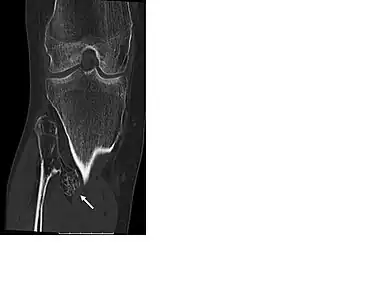

multiple osteochondromas around the knee

CT of osteochondroma in MO